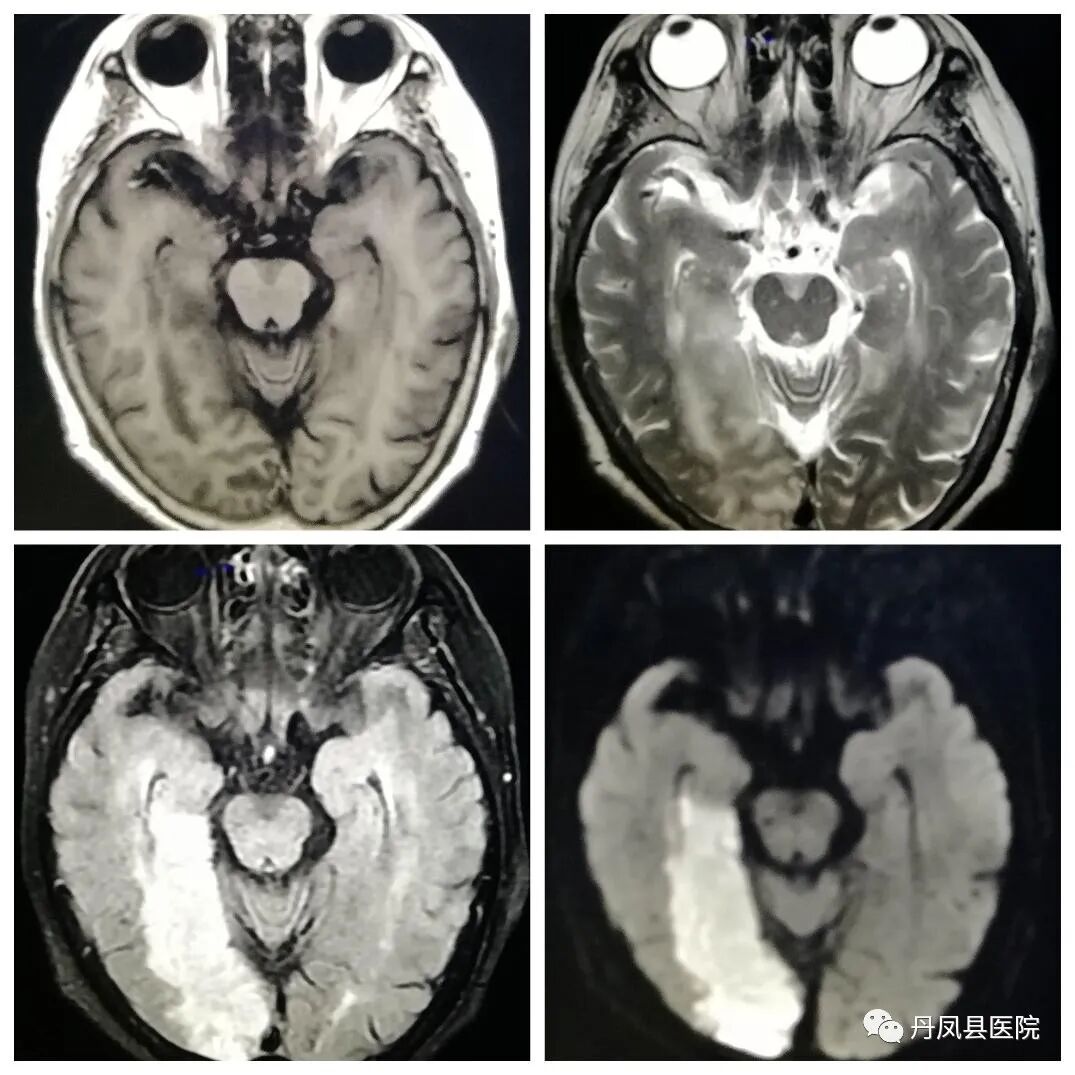

开展项目MRI磁共振设备是我县第一台检查设备,其扫描速度快、噪音低、图像分辨率高,能够进行全身各部位磁共振平扫、增强扫描及血管成像(MRA、MRV)、功能成像(DWI、DTI、SWI、MRS)、灌注成像、胰胆管水成像(MRCP)、泌尿系水成像(MRU)等检查。尤其在中枢神经系统、胆道系统、脊柱判断新旧骨折、骨转移瘤、早期股骨头缺血坏死、关节软骨损伤、韧带肌腱损伤有不可替代的优势,为临床提供更多、更丰富的影像诊断信息。磁共振的多方位、多参数、多轴倾斜断层对中枢神经系统病变的定位、定性诊断极其优越。中枢神经系统疾病的诊断中,除颅骨骨折和颅内急性出血不及CT外,在脑部肿瘤、颅内感染、脑血管病变、脑白质病变、脑发育畸形、脑退行性病变、脑室及蛛网膜下腔病变、脑挫伤、颅内亚急性血肿及脊髓的肿瘤、感染、血管性病变及外伤的诊断有明显优势。

急性脑梗死

脑膜瘤